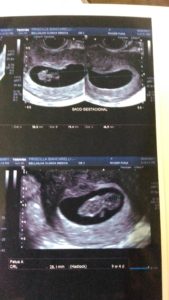

O que os olhos não vêem o coração não sente… E chegou o dia do primeiro ultrassom!!

Pronto, mesmo já sentindo tudo aquilo acontecendo dentro de você uma imagem foi capaz de provar que sim, havia alguém me habitando!

A insegurança foi embora e a notícia foi amplamente divulgada!!